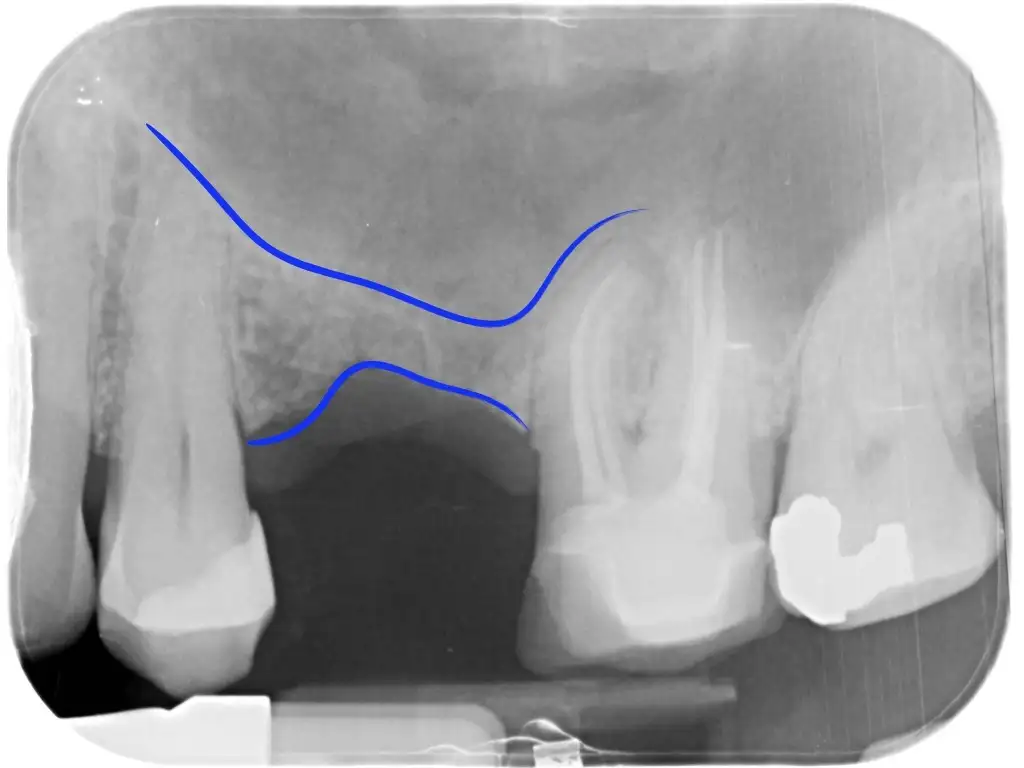

Vi sono un’ampia serie di tecniche sempre più perfezionate che permettono di ricreare il volume osseo riassorbito per poter posizionare in seguito o nella stessa seduta l’impianto.

Si può aumentare lo spessore della cresta ossea perché troppo sottile o l’altezza perché troppo bassa. Questa è la soluzione ideale quando mancano solo alcuni denti e permette di ottenere ottimi risultati quando opportunamente progettata ed eseguita attraverso i più rigidi protocolli chirurgici e di sterilità.